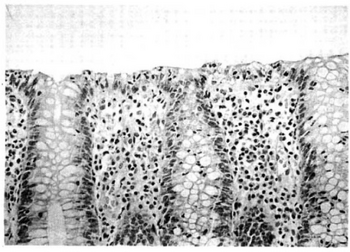

Micrograph of lymphocytic colitis. HPS stain.

Biopsy specimen obtained from a individual diagnosed as lymphocytic colitis

The colonoscopy is normal but histology of the mucosal biopsy reveals an accumulation of lymphocytes in the colonic epithelium and connective tissue (lamina propria). Collagenous colitis shares this feature but additionally shows a distinctive thickening of the subepithelial collagen table.[1][2]